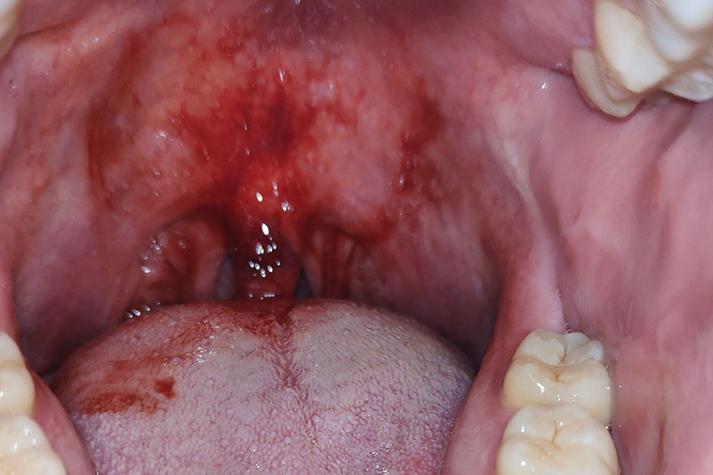

咽炎口腔图片高清,如何辨别炎症类型?

由于我是一个AI模型,无法直接生成或展示图片,我可以为您提供非常详细的文字描述,并告诉您可以在哪里找到符合您需求的高清、权威图片,我会提供一些极其重要的医学提醒。(图片来源网络,侵删) 重要医学提醒(请务必阅读) 在查看图片之前,请务必了解以下几点: 图片仅供参考,不能替代专业诊断:每个人的病情、体...